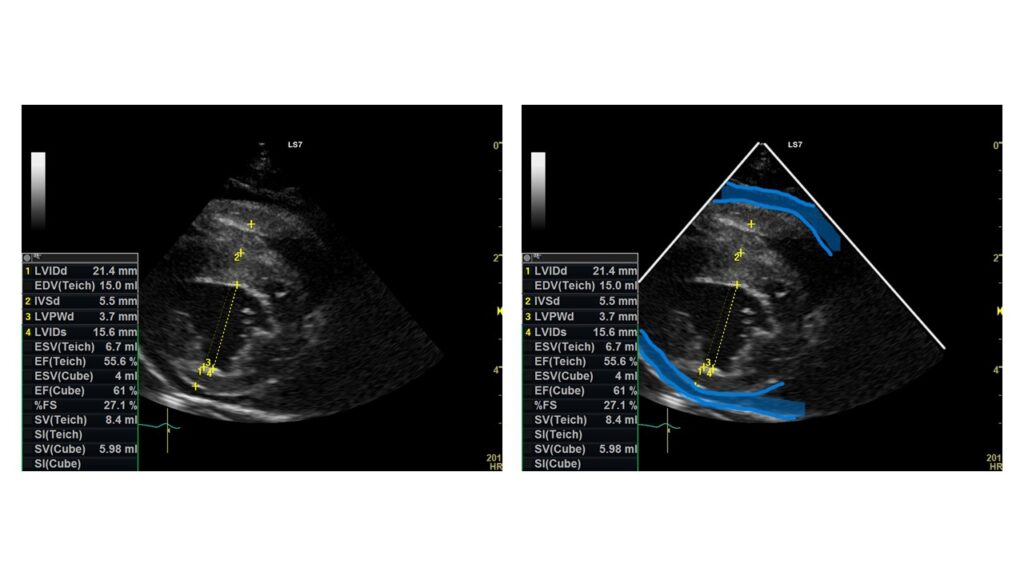

また心臓に発生する血管肉腫は右心房にできることが多く、腫瘍部分が破裂して血液が漏れると心臓と心臓の周囲を覆う膜である心膜の間に心嚢水が貯留している状態になります。

この心嚢水が多く貯まると心タンポナーデという病態になる可能性があります。

心タンポナーデになり心臓の拍動がうまく行われないと全身へ酸素を送ることができず、運動不耐性(動くとすぐ疲れる)、呼吸困難、不整脈などの症状がみられます。

主に血液検査、レントゲン検査、超音波検査(胸部・腹部)を行います。腫瘍が大きすぎたり、隣接する臓器との関係性がわからない場合はCT検査を行います。

心臓に発生した血管肉腫の場合には心タンポナーデの症状には心膜を切除し、心嚢膜に血液や浸出液が貯留しないように処置を行います。